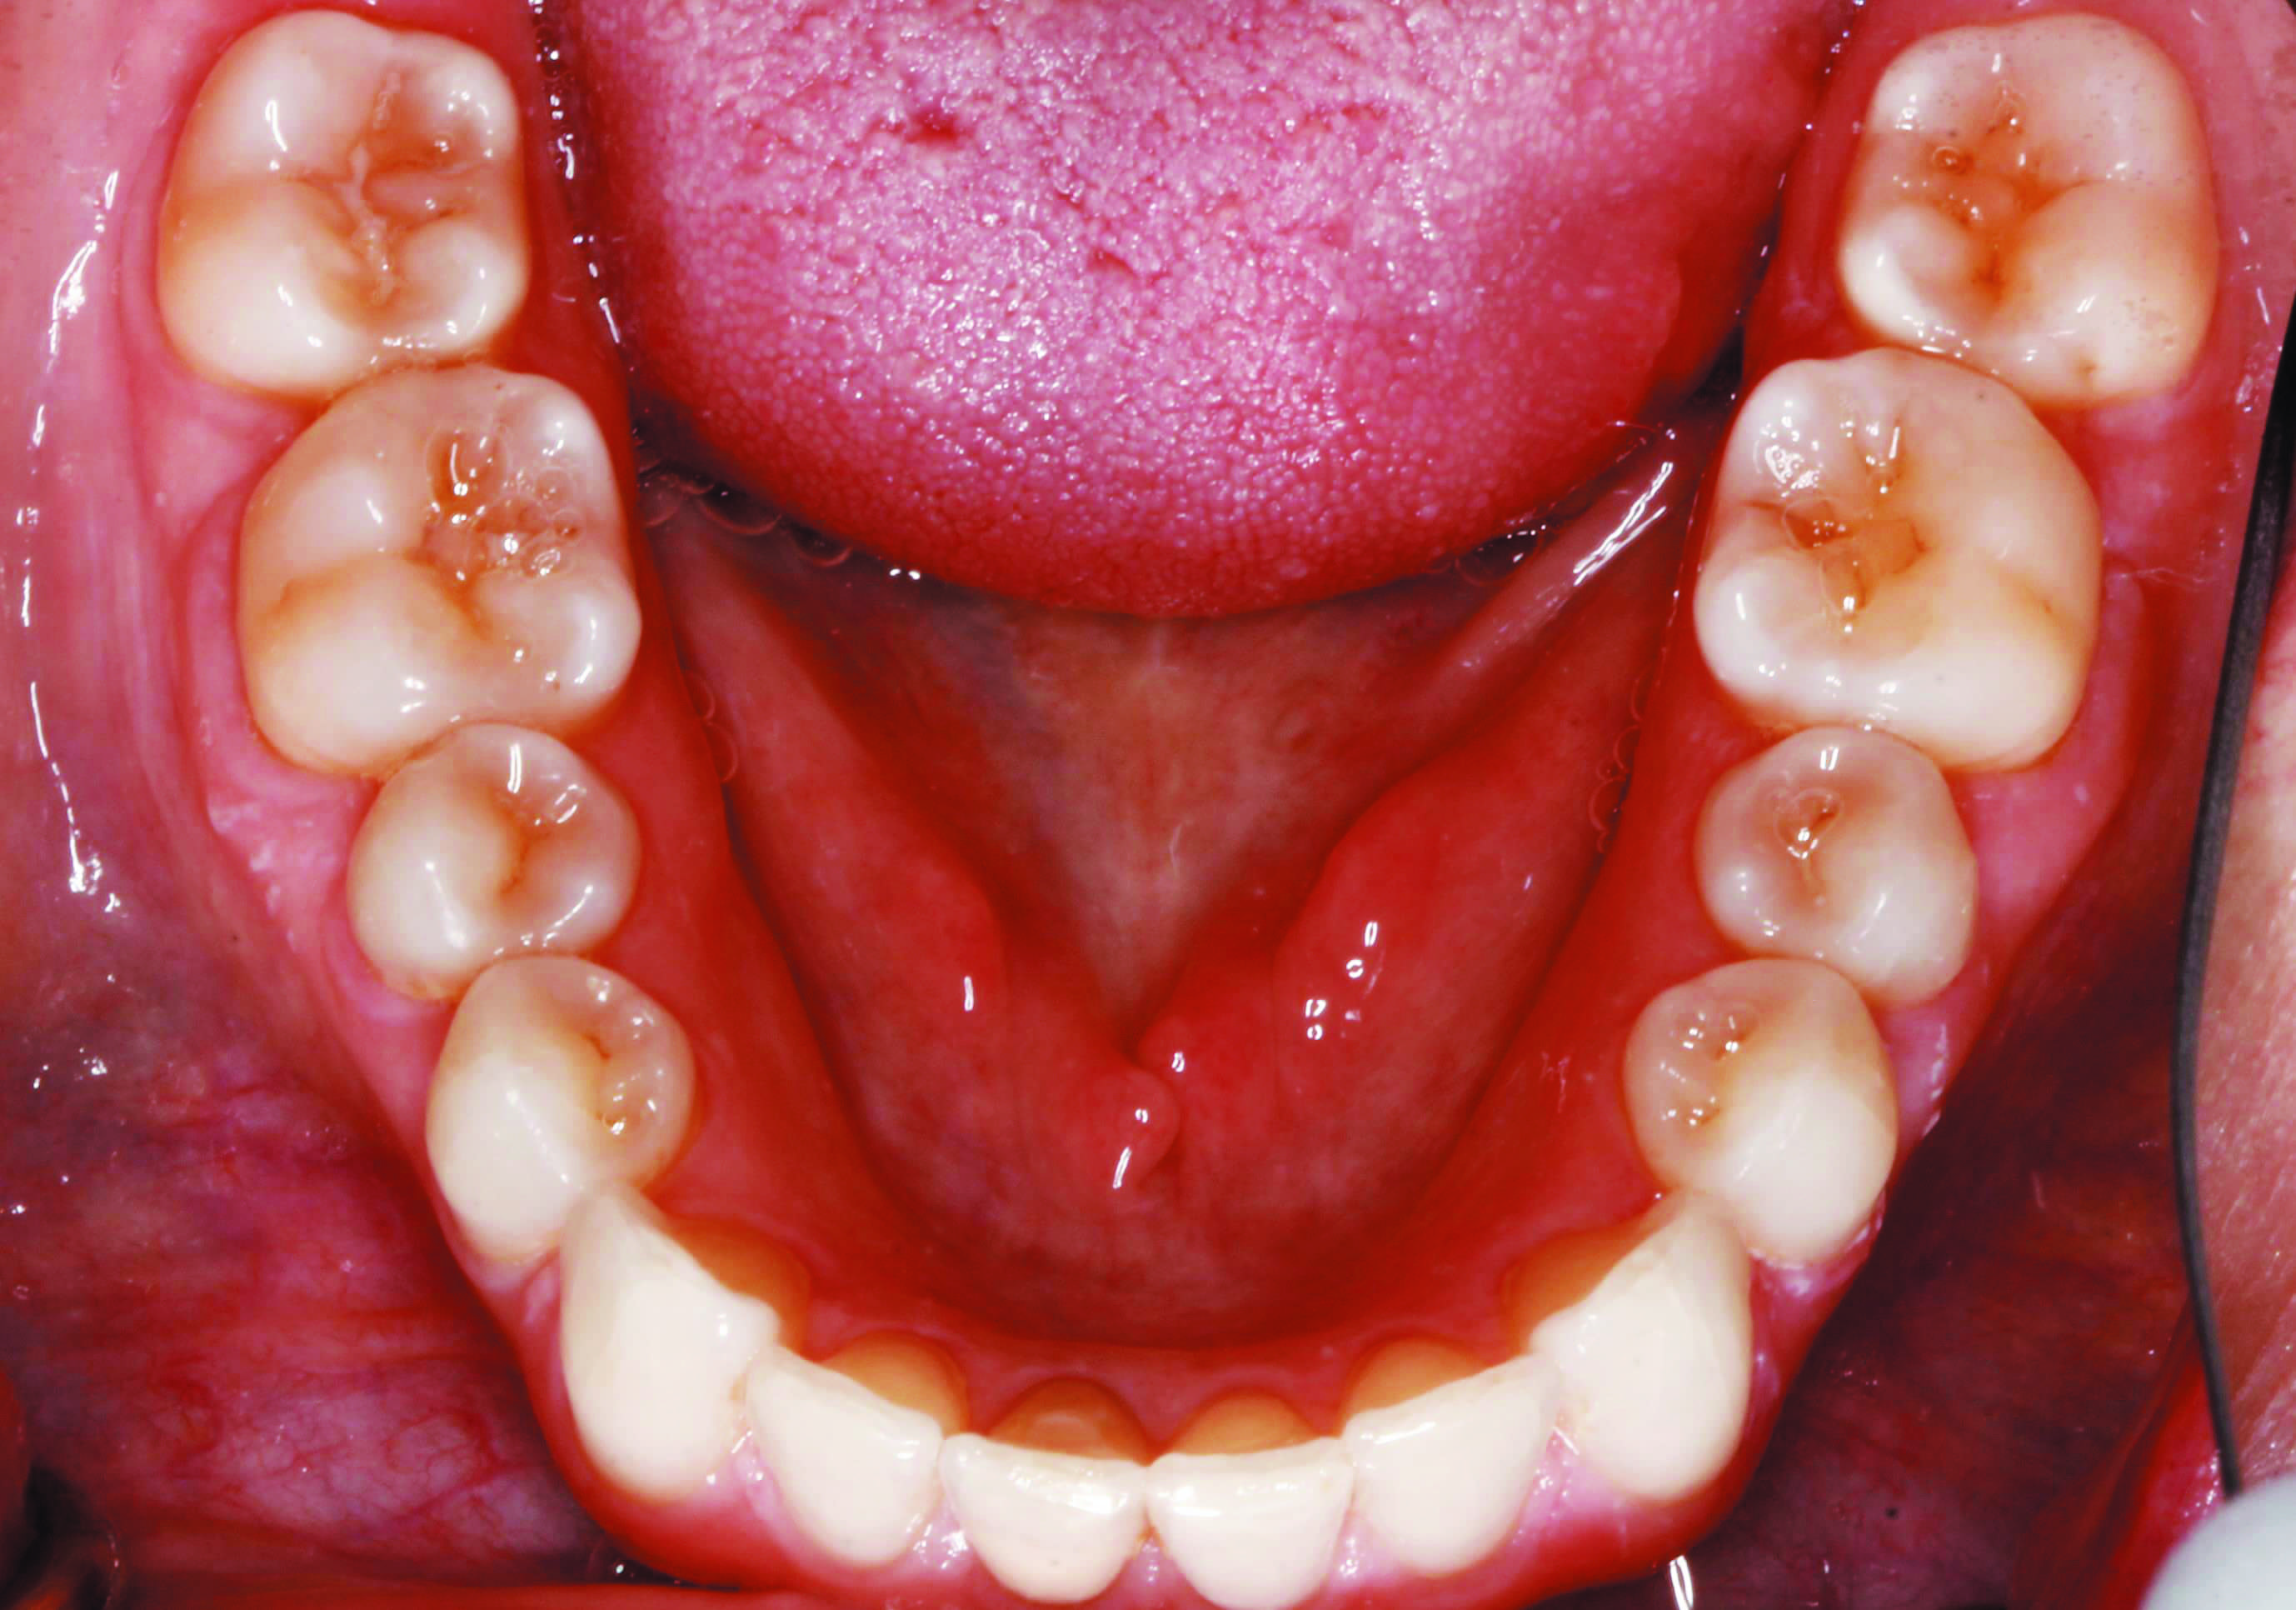

Before and after 14 aligner trays and 13 refinement trays D Aligner Refinement It is not a bad thing if your dentist suggests refinements, it just means that they are making sure you get the most out of your treatment. Each aligner is designed to put the right amount of pressure on your teeth to move and realign them into their ideal positions. Invisalign refinements are corrections to your aligner treatment after you. Aligner Refinement.